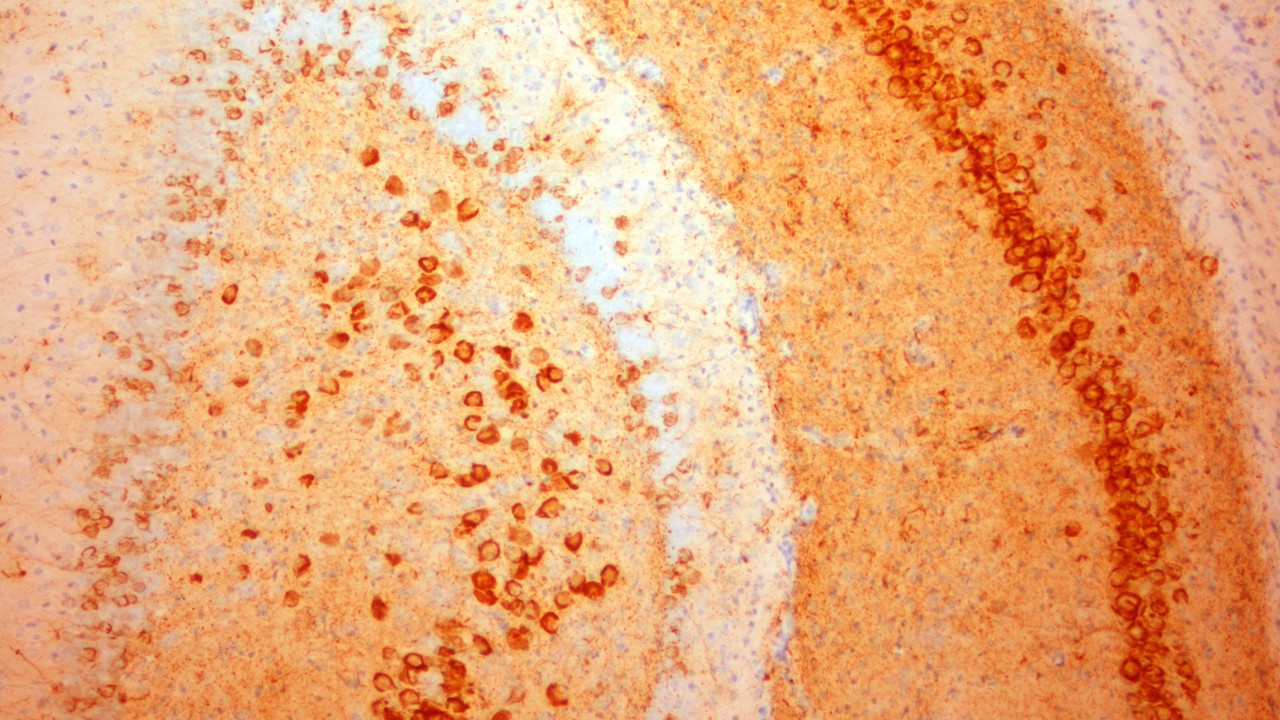

El cerebro es el órgano más complejo del cuerpo humano. Y uno de los más importantes. Está compuesto por miles de millones de neuronas y es parte del sistema nervioso central que controla todo, desde nuestros sentidos hasta los músculos de todo el cuerpo.

En Lundbeck, trabajamos sin descanso para recuperar la salud mental, para que cada persona pueda ser la mejor versión de sí misma. Para Lundbeck, nadie debería verse afectado por una enfermedad mental que le impida tener una buena calidad de vida.